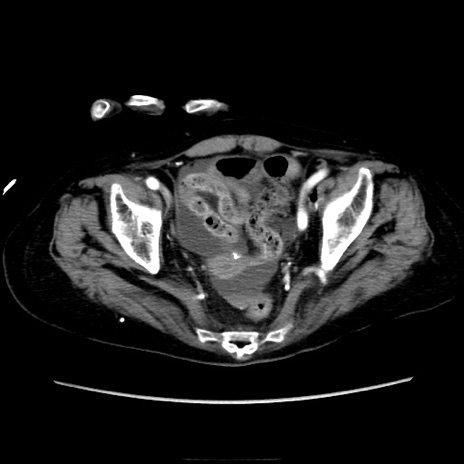

症例40(横断像)

横断像